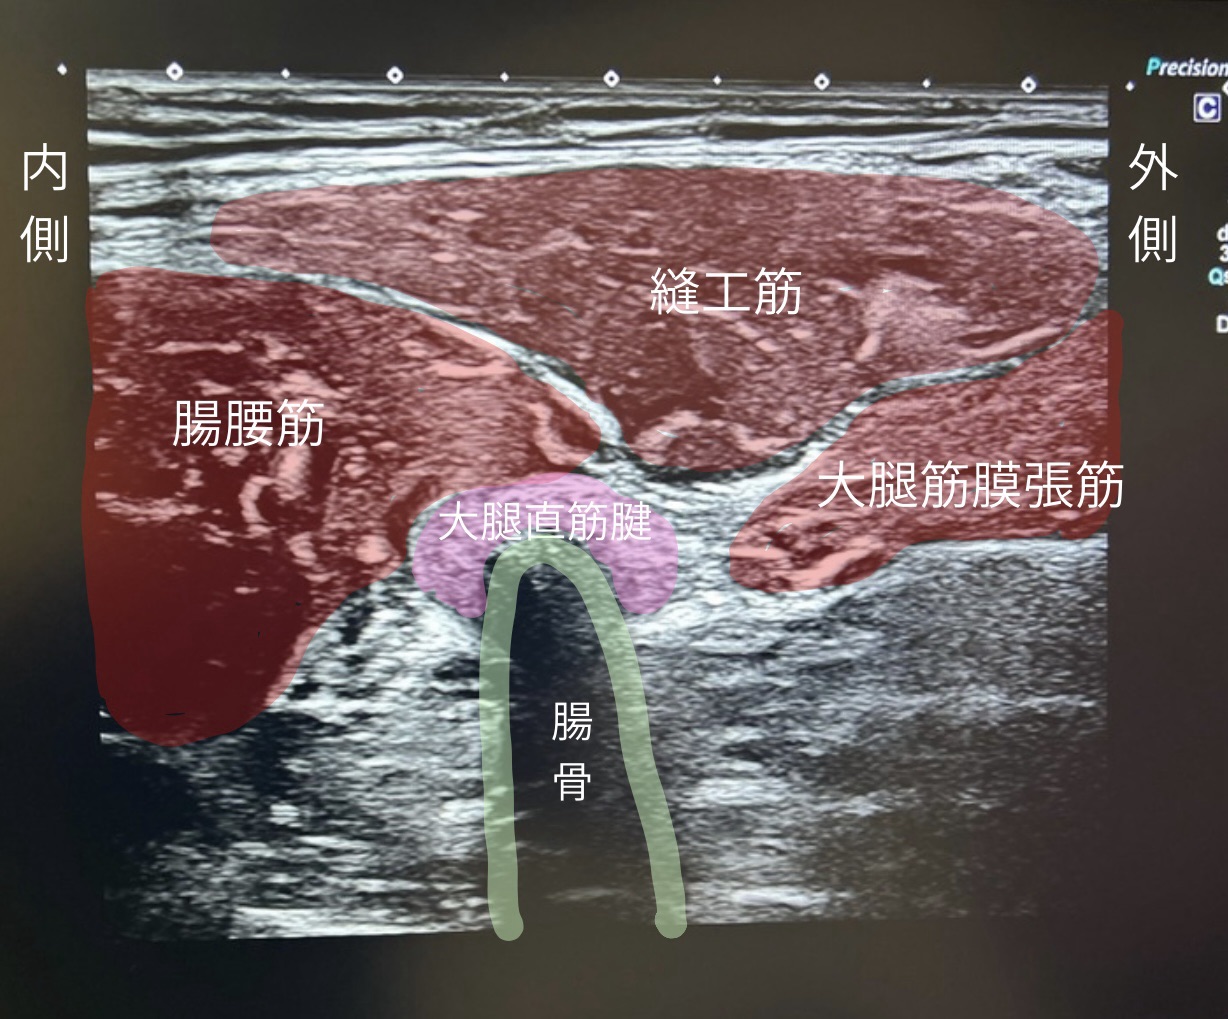

▶ エコー(超音波検査)

・出血や腫れの有無

・筋肉や腱の損傷、骨の付着部の損傷(裂離骨折)の確認

・筋肉の収縮動き